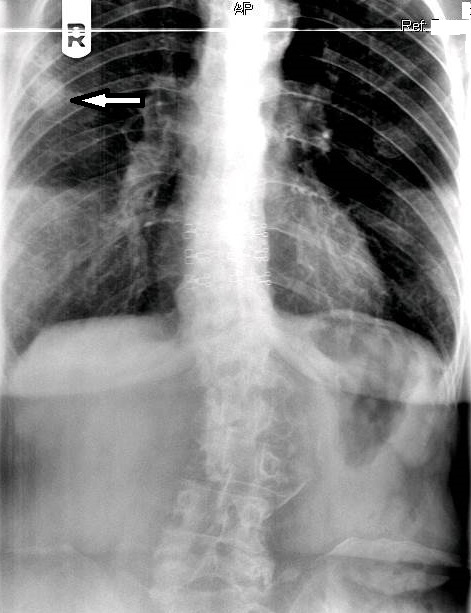

On figure 1, the original AP thoracic projection, an oval density is seen in the periphery of the right lung field (white arrow points to lesion). A thoracic and lumbar scoliosis is also seen. The lateral projection revealed multilevel degenerative change, as well as compression fractures at T9 and T10, with a focal kyphotic deformity seen in figure 2. Since a PA chest projection was not included, a chest series consisting of PA and lateral views was suggested to better evaluate the suspected lesion.